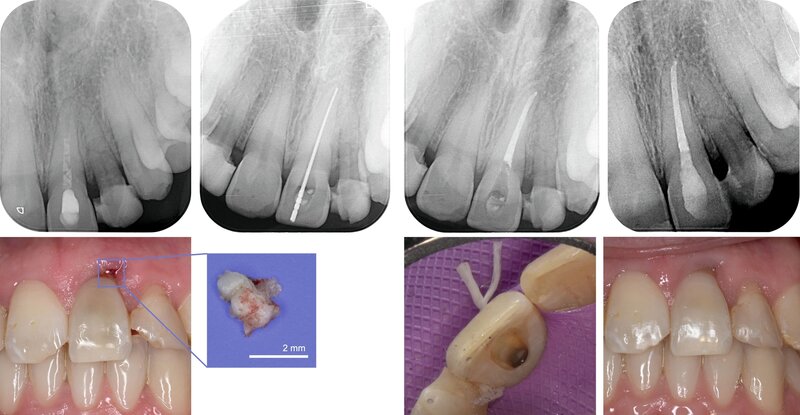

Bei der Nachkontrolle eine Woche später wurde ein Wechsel der medikamentösen Einlage zu Kalziumhydroxid im Zahn 21 durchgeführt. In regio 21 persistierte vestibulär eine offen granulierende Wunde. Zahn 22 reagierte weiterhin verzögert positiv auf die Sensibilitätstestung und durch eine Röntgenkontrollaufnahme ergab sich der Verdacht auf eine Wurzelfraktur (Abbildung 2B).

Nach sieben Wochen Schienungsdauer wurde der TTS schließlich entfernt. Zahn 21 zeigte sich klinisch gräulich verfärbt, reizfrei und mit Lockerungsgrad (LG) 0. Zahn 22 war weiterhin gelockert (LG II). In der aktuellen Röntgenkontrollaufnahme waren nun deutlich erkennbare Frakturspalte im mittleren Wurzeldrittel sichtbar (Abbildung 2C). Eine Kommunikation zur Mundhöhle konnte durch zirkuläre Sondierung des Sulkus ausgeschlossen werden und bei erneuter Sichtung des CT-Datensatzes konnte auf einen intraalveolären Verlauf der Fraktur geschlossen werden.

In der Zwischenzeit erfolgten eine reguläre Befunderhebung (Abbildung 4), eine professionelle Zahnreinigung und Mundhygieneinstruktion sowie die restaurative Versorgung kariöser Läsionen an Zahn 25 mesial und Zahn 16 mesial-okklusal (Abbildung 5). In der Röntgenkontrolle neun Monate nach dem Trauma zeigten sich keine Hinweise auf externe Resorptionen. Die endodontische Behandlung von Zahn 21 konnte daraufhin abgeschlossen werden.

Zusätzlich wurde in Regio 21 ein kleiner Knochensequester entfernt (Abbildung 6). Zu einer Sequestration kommt es häufig bei einer Infektion des Alveolarknochens, wobei dessen vollständiger Abbau meist nicht gelingt, so dass der verbliebene Knochensequester über Monate von Granulationsgewebe umgeben und schließlich abgestoßen wird [DGMKG und DGZMK, 2022].